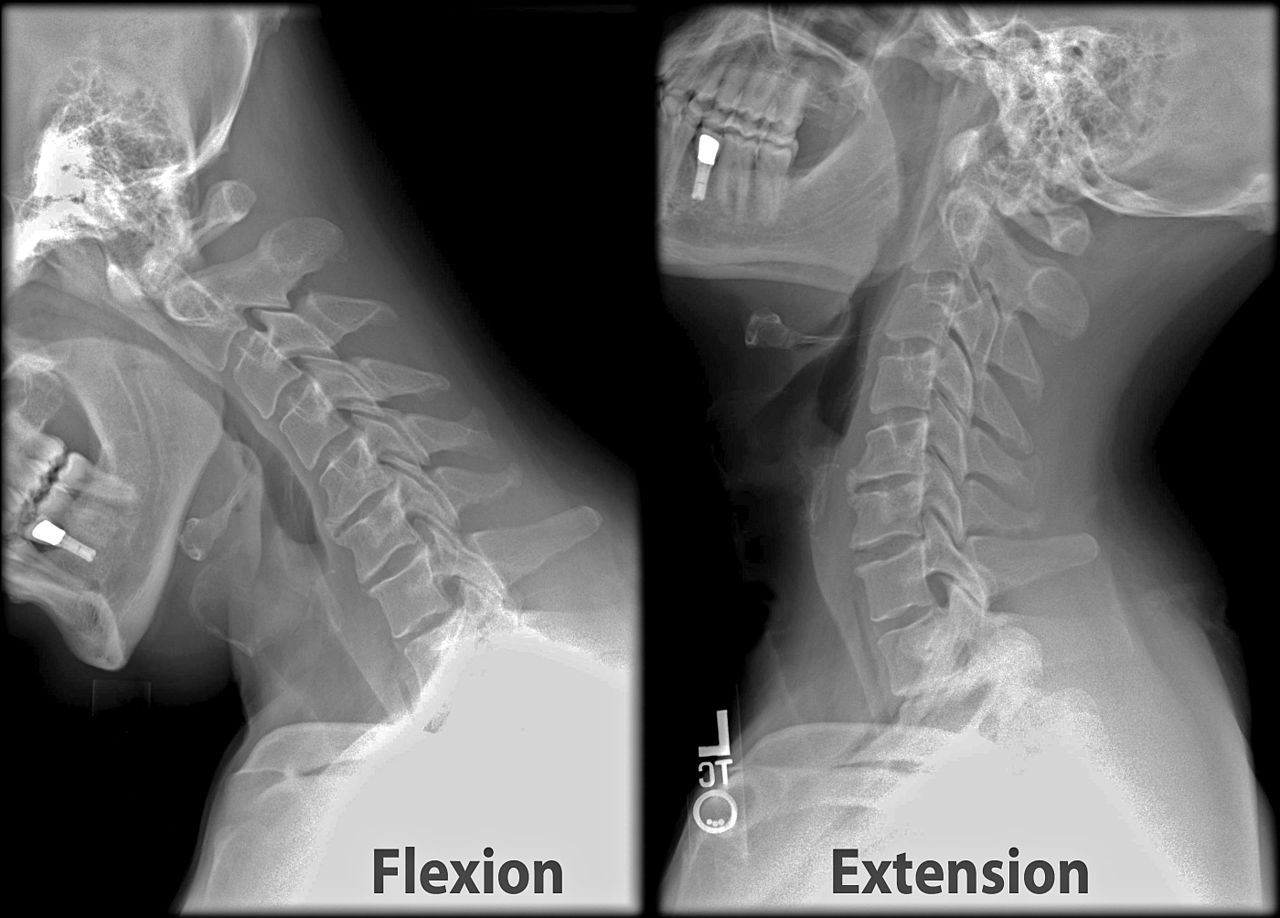

경추의 엑스레이 이미지(X-ray of cervical vertebrae)